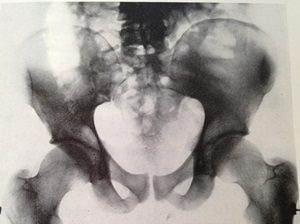

In John Berger’s And Our Faces, My Heart, Brief as Photos, on the very last page, he writes: “What reconciles me to my own death more than anything else is the image of a place: a place where your bones and mine are buried, thrown, uncovered, together. They are strewn there pell-mell. One of your ribs leans against my skull. A metacarpal of my left hand lies inside your pelvis. (Against my broken ribs your breast like a flower.) The hundred bones of our feet are scattered like gravel.

It is strange that this image of our proximity, concerning as it does mere phosphate of calcium, should bestow a sense of peace. Yet it does. With you I can imagine a place where to be phosphate of calcium is enough.”[iv]

“What reconciles me to my own death more than anything else is the image of a place: a place where your bones and mine are buried, thrown, uncovered, together…A metacarpal of my left hand lies inside your pelvis.”